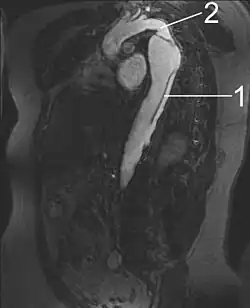

1 Aorta descendens mit Dissektion

2 Linke Schlüsselbeinarterie

3 Aorta ascendens

2 Aortenisthmus

Ähnlich exakt und umfassend ist die Darstellung in der MRT, für die kein iodhaltiges Kontrastmittel benötigt wird und die auch eine zuverlässige Beurteilung der Aortenklappe erlaubt. Die MRT erzielt mit jeweils fast 100 % die beste Sensitivität und Spezifität für die Diagnose einer Aortendissektion.